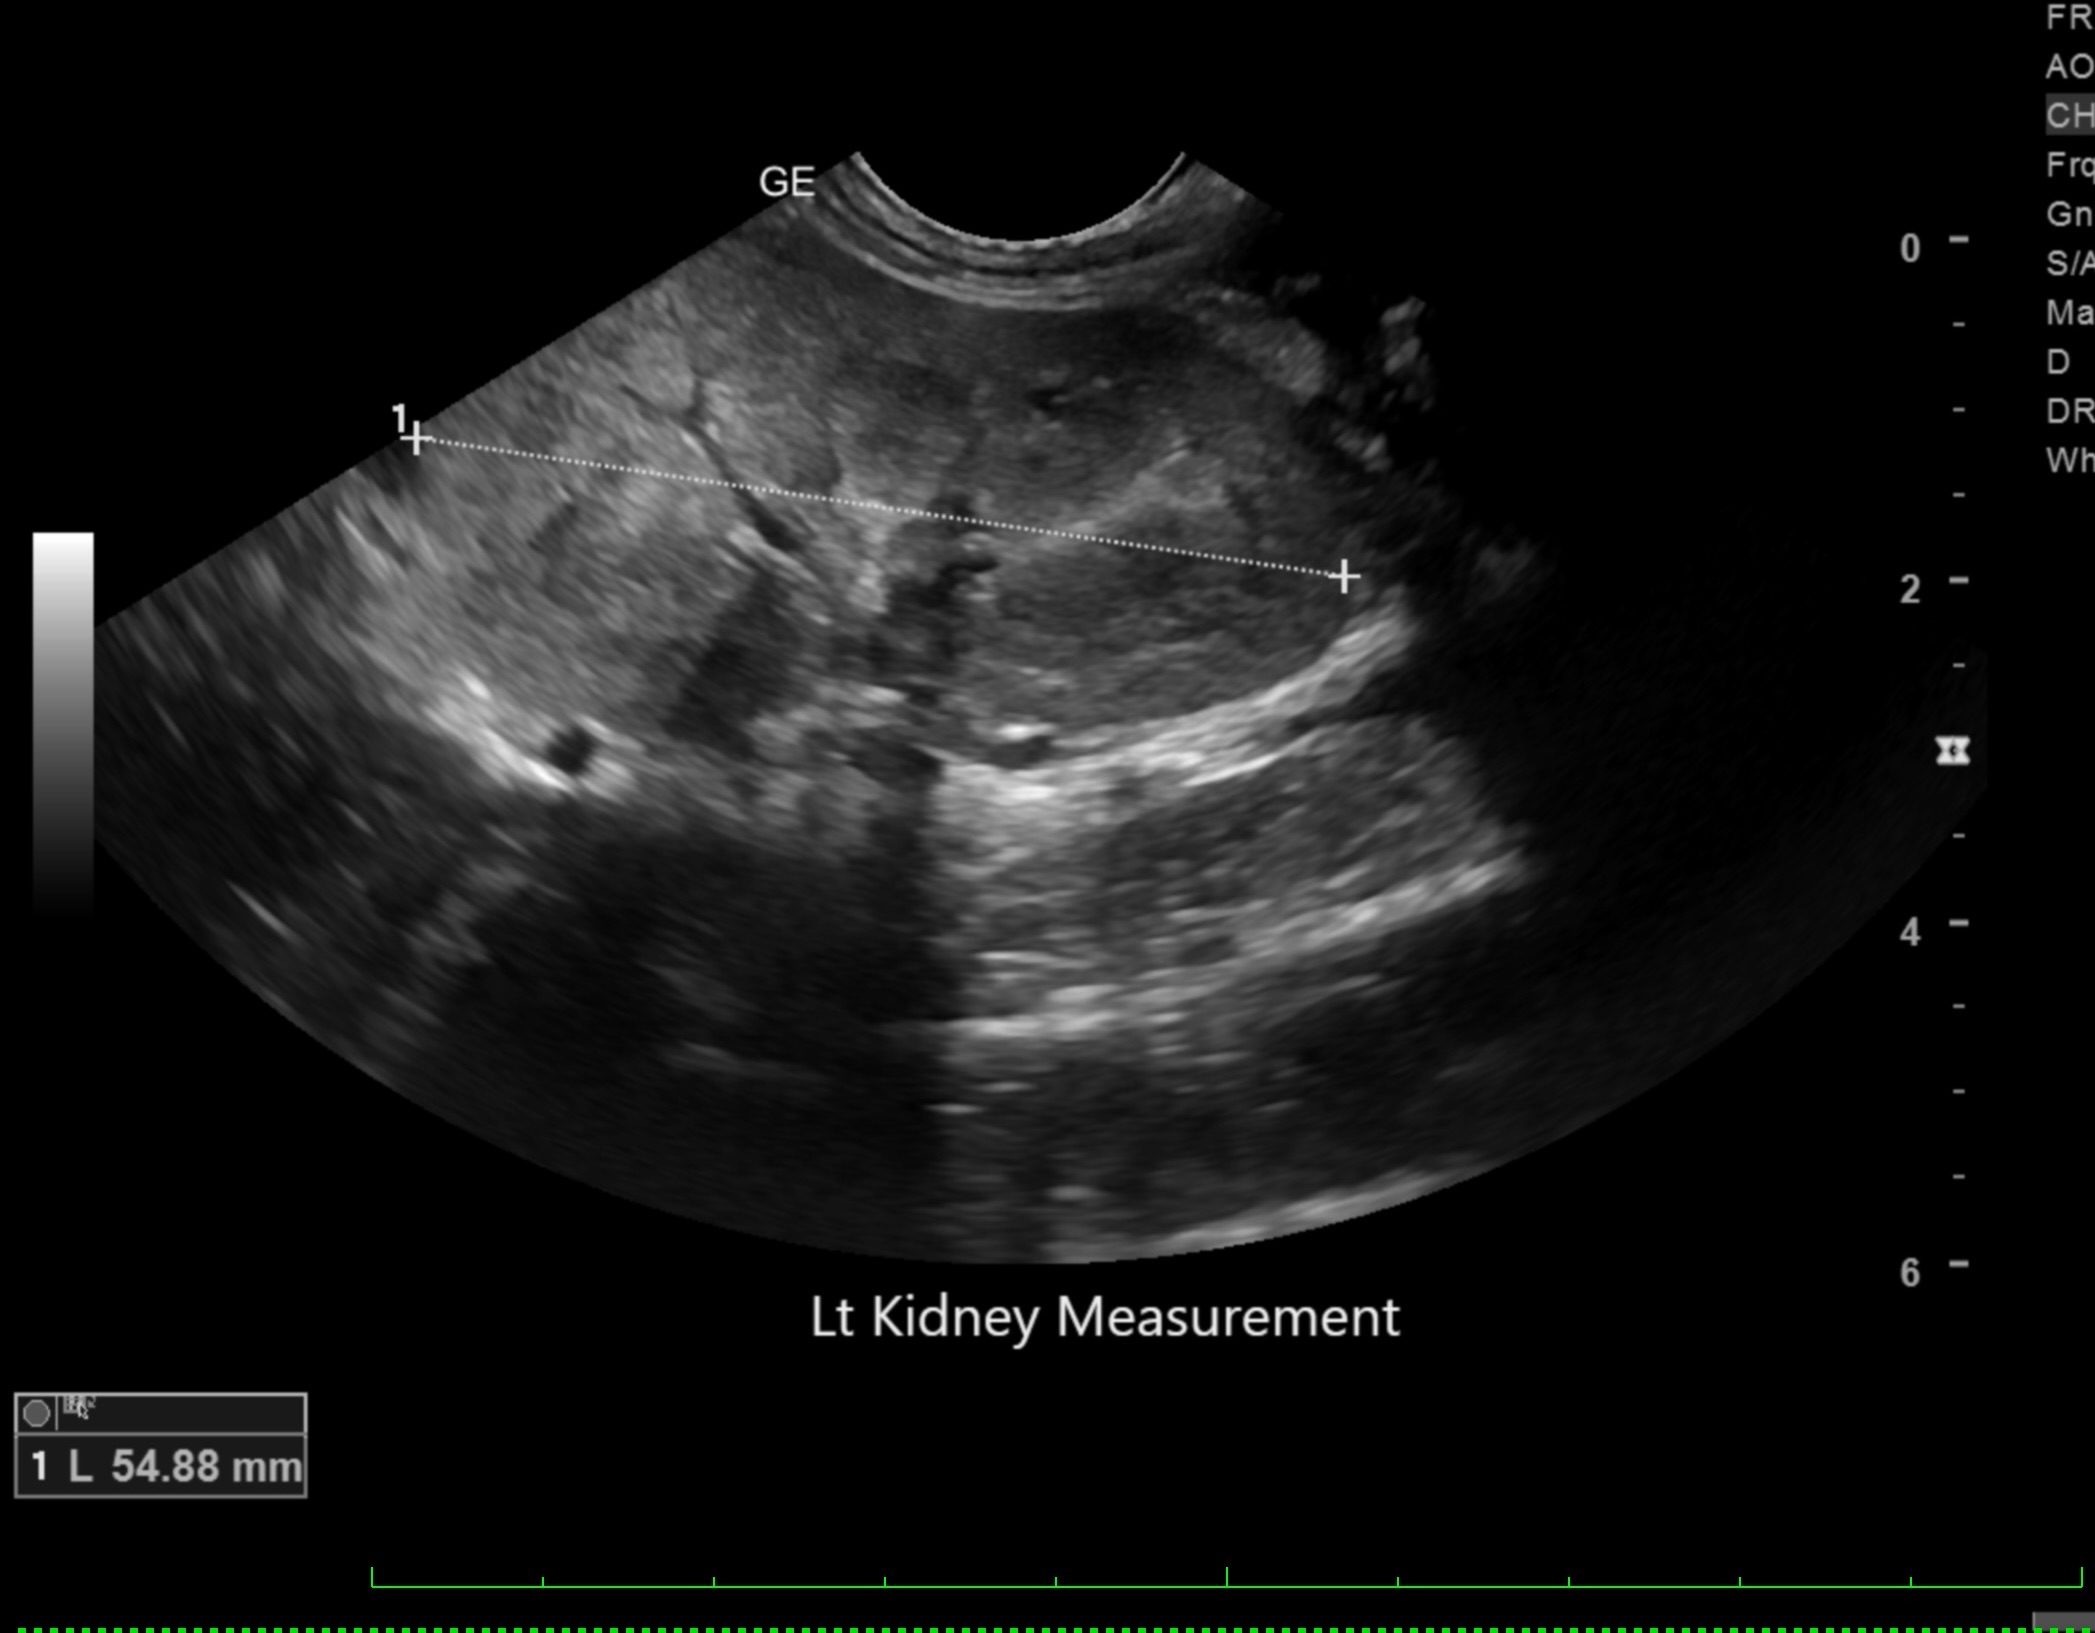

Labwork (fasted): TP 4.5, Alb 2.5, ALP 144, ALT 155, GGT 3, Bili 0.4, Cre 0.3, Cho 51, Amy 266 CBC – HCT 39%, Hgb 12.0 UA – USG 1.030pH 6, 1+ bilirubin, WBC 4-10/hpf, rods 26-50/hpf Negative Accuplex Bile Acids: Pre 299.2, Post-meal – 90.7